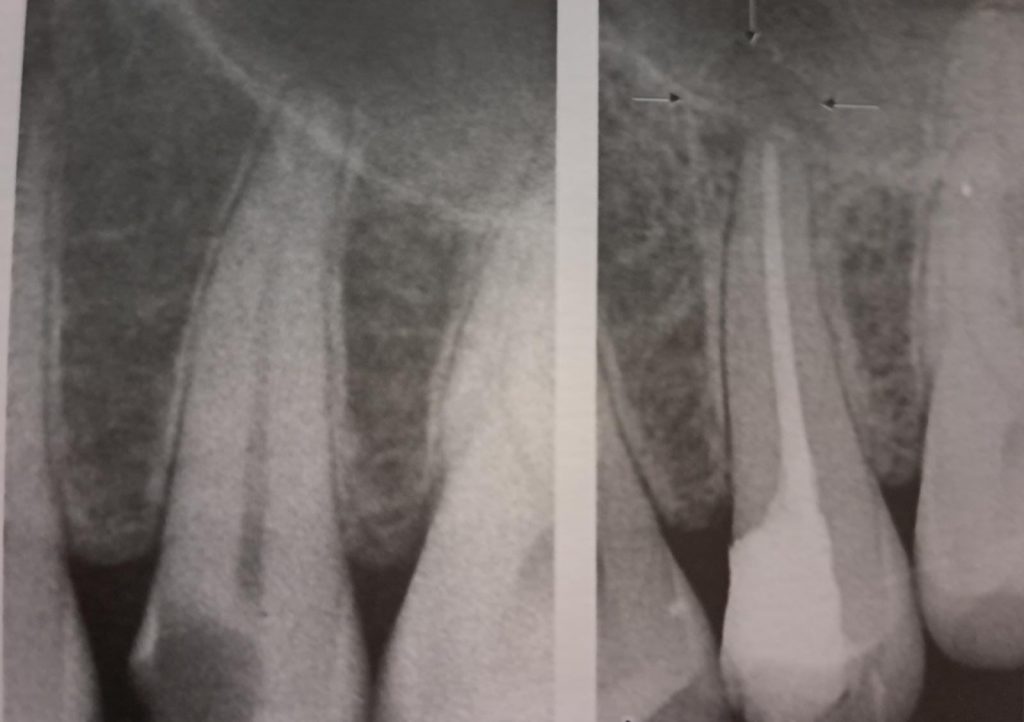

In questa fase l’unico trattamento che può evitare l’estrazione del dente conservando la sua struttura è la terapia endodontica, o cura canalare, conosciuta da tutti come devitalizzazione, che consiste nella rimozione della polpa (nervo dentale) presente all’interno del dente e per tutta la lunghezza delle radici, e nella sua sostituzione con un’otturazione permanente in guttaperca e cemento canalare, previa adeguata detersione, disinfezione e sagomatura dei canali radicolari e in seguito la ricostruzione della corona.